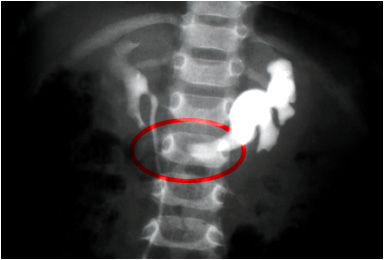

Riñón en herradura

Pielografía que muestra el contorno de la pelvis renal derecha y una dilatación pielocaliciario izquierdo. El circulo rojo muestra la sombra de la masa renal fusionada colocada frente a la segunda vertebra lumbar .